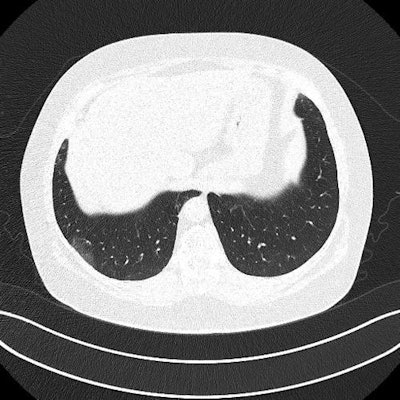

Ultrasound and CT images from a 62-year-old woman with long-term COVID-19 symptoms. The patient, who was not part of the study, visited the Madrid emergency department with persistent dyspnea and cough. The ultrasound image (above) shows an irregular pleural line and some B-lines, which correlate to ground-glass opacities in the lower lobes on CT (below). Images courtesy of Dr. Yale Tung-Chen, PhD.

The patients underwent both lung ultrasound and chest CT scans, which revealed a variety of abnormalities related to COVID-19:

- The 35-year-old woman had a mild, irregular pleural line and B-lines in her right anterior chest on ultrasound, which correlated with ground-glass opacities on CT.

- The 41-year-old woman had an irregular pleural line in her right lateral area on ultrasound, which correlated with pleural thickening on CT.

- The 64-year-old man had a marked, irregular pleural line and multiple B-lines on ultrasound, which correlated with fibrotic changes on CT.